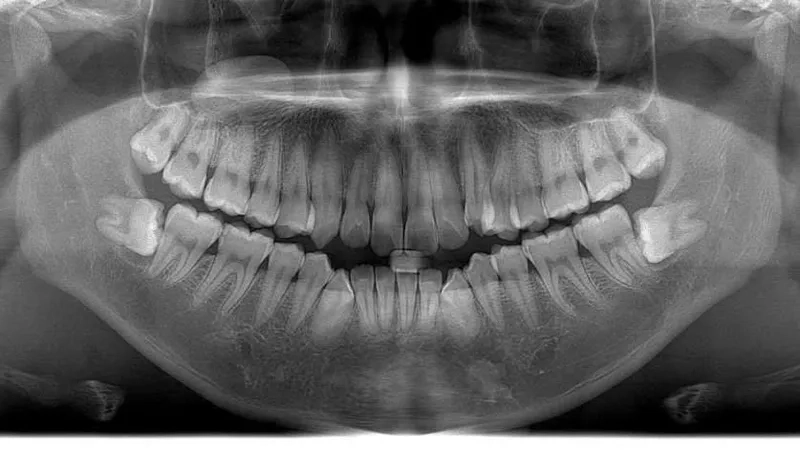

Chính vì là kẻ đến sau cùng, răng khôn thường không tìm được vị trí thuận lợi để mọc thẳng. Chúng phải tìm cách chen chúc, dẫn đến các tình trạng phổ biến như mọc lệch, mọc ngầm dưới nướu hoặc đâm ngang vào chiếc răng số 7 bên cạnh.

Hủy hoại cấu trúc răng số 7 lân cận

Khi răng khôn mọc lệch hoặc đâm ngang, nó sẽ trực tiếp húc vào chân răng số 7. Lực đẩy này diễn ra âm thầm nhưng mạnh mẽ, làm tiêu chân răng, gây sâu răng số 7 và có thể khiến chiếc răng này bị lung lay hoặc mất vĩnh viễn.

Xô lệch toàn bộ hệ thống hàm răng

Vì xương hàm không còn đủ chỗ, răng khôn khi cố gắng vươn lên sẽ tạo ra một áp lực đẩy rất lớn lên các răng phía trước. Điều này khiến cả hàm răng bị chen chúc, xô lệch và làm hỏng kết quả của những người đã từng thực hiện chỉnh nha.

Nguy cơ hình thành u nang xương hàm

Trong một số trường hợp răng khôn mọc ngầm hoàn toàn trong xương, các mô bao quanh răng có thể phát triển thành u nang.

Nếu không được phát hiện qua phim chụp X-quang, u nang này sẽ âm thầm phá hủy xương hàm, làm tổn thương các dây thần kinh và các răng xung quanh, gây ra những tổn thương nặng nề khó phục hồi.